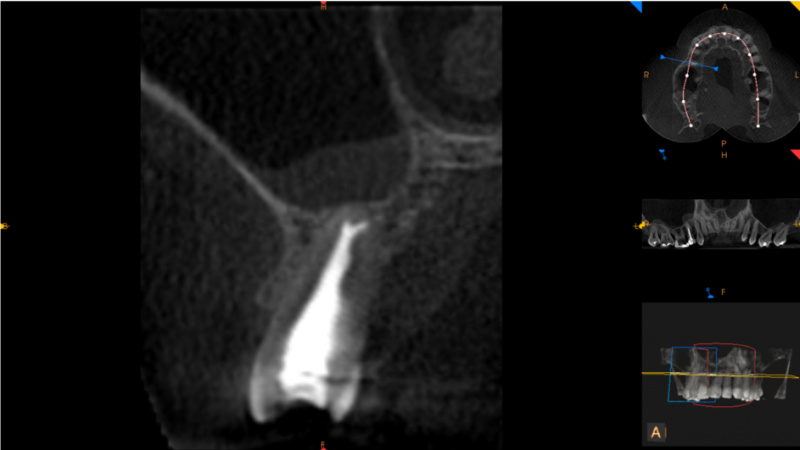

Na wysokości zębów 17,27 w linii pośrodkowej podniebienia widoczny guz tkanek miękkich (16mm x 13,5mm x 16mm). Zmiana powoduje modelowanie kości podniebienia. Po stronie prawej tkanka kostna miejscowo niewidoczna (możliwe połączenie z jamą nosową) – do konsultacji chirurga szczękowo – twarzowego.

Ząb 17 – bez znamion leczenia kanałowego. Szpara ozębnej wokół wierzchołka korzenia podniebiennego poszerzona.